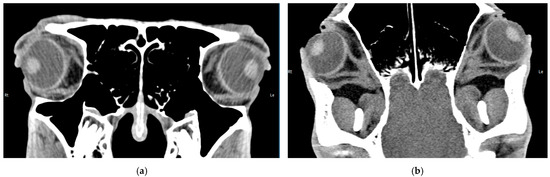

Intraocular Tumors in Horses: Diagnosis, Tumor Classification, Oncologic Assessment and Therapy

Intraocular neoplasia in horses is rare and only few case reports and small case series exist. Intraocular neoplasia has various clinical signs and includes important differential diagnoses in ocular disease. This narrative review of the current literature aims to provide a clinically relevant [...] Read more.

Intraocular neoplasia in horses is rare and only few case reports and small case series exist. Intraocular neoplasia has various clinical signs and includes important differential diagnoses in ocular disease. This narrative review of the current literature aims to provide a clinically relevant overview and classification of intraocular tumors in horses and adds a comparative oncological perspective concerning diagnosis, treatment and future considerations. The available clinical and imaging examination techniques allow for a reliable and differentiated investigation of the tumor, even in the standing horse, using high-frequency ultrasound or optical coherence tomography, which have gained importance in equine ophthalmology. Sectional imaging techniques, in particular computed tomography, are suitable for the examination of the peribulbar, retrobulbar and orbital structures. Differentiated diagnostics including precise tumor staging (TNM: tumor, node, metastasis) are essential for a general prognostic and therapeutic assessment. The embryologic and anatomic tissue origin of the neoplasm is the basis for clinicopathologic classification. Medulloepithelioma and uveal melanocytic neoplasia are the most common intraocular tissue formations occurring in horses. Whereas melanocytic neoplasia of the iris can be treated surgically, neuroepithelial tumors regularly lead to bulbus extirpation. Other primary intraocular neoplasms are sporadically reported, as well as intraocular metastasis of systemic neoplasia. Chemotherapy and radiation therapy are not currently used to treat intraocular neoplasia in horses and need to be further investigated, especially regarding the latest developments in human and small animal medicine. In addition, horses and dogs may serve as models for human oncologic research. Full article